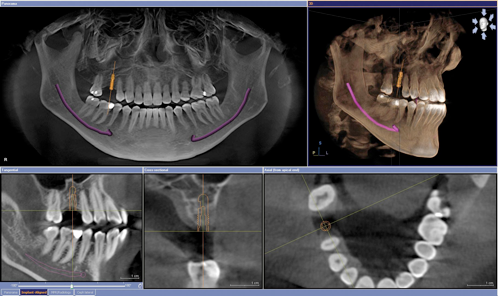

Najmä pre zubné implantáty je potrebný CT scan – 3D snímok, ktorý vie určiť presnú diagnostiku, ktorá je pri zavádzaní zubných implantátov veľmi dôležitá pre spodnú ako aj pre hornú čeľusť.

Pomocou 3D scanu sa dosiahne kompletná a presná trojrozmerná replika tvárovej časti.

Naša technológia CBCT Scan/3-Dimensional Imaging je nesmierne dôležitá pri plánovaní ošetrenia a diagnostikovaní

Existuje mnoho postupov vykonávaných stomatologickými odborníkmi, ktoré vyžadujú osobitné kontroly. Je nutné získať úplný prehľad o stave kostného tkaniva pacienta pred zubným ošetrením, kde je nutné použiť zubné implantáty. To môže byť uľahčené pomocou počítačovej tomografie (CT). Tento postup je veľmi podobný konvenčným röntgenom, ale stav chrupu ukazuje podrobnejšie v 3-dimenzionálnom priereze skenovanej oblasti a tak poskytuje potrebné informácie pre bezpečnú a účinnú liečbu zubov.

CT vyšetrenie sa líši od konvenčného snímku v mnohých spôsoboch. Najdôležitejšie je, ako sa získava obraz. Pri konvenčnom röntgéne je jediný záblesk žiarenia smerovaný do kosti / alebo tkaniva v určitej oblasti. Tieto lúče potom prejdú na fotografický film. Tento záblesk žiarenia vykreslí biele kosti a štruktúru tkanív a výsledok sa objaví aj v rôznych odtieňoch šedej. Skenovanie pomocou 3D skeneru umožňuje Vášmu zubárovi zhodnotiť zdravotný stav čeľustnej kosti oveľa podrobnejšie a tým umožní aj lepší celkový výsledok. Konkrétne CT skener zahŕňa prepustenie niekoľkých malých žiarení, ktoré sú namierené z rôznych uhlov na skúmanej oblasti a tým sa dosiahne 3D efekt.